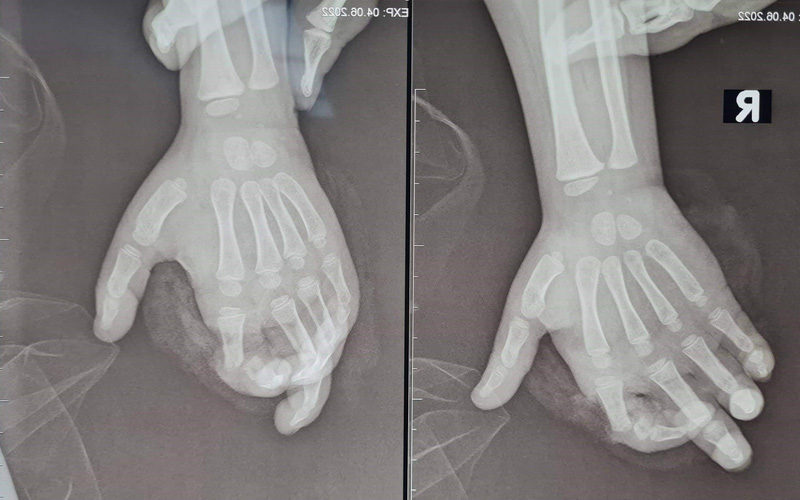

TS.BS Nguyễn Quang Vịnh, Khoa Phẫu thuật Chi trên và Vi phẫu thuật, Bệnh viện Trung ương Quân đội 108 cho biết: Kết quả thăm khám xác định bệnh nhi vào viện giờ thứ 4 do bị máy nghiền hoa quả nghiền vào bàn tay phải. Sau tai nạn, bệnh nhi bị đứt gần rời ngón 2 tay phải, phần ngón đứt gần rời lủng lẳng, trắng bệch do không được cấp máu.

Các bác sĩ phải kết lại xương, khâu nối gân duỗi, nối thần kinh và đặc biệt là phải nối lại mạch máu (gồm các động mạch và tĩnh mạch) để cung cấp lại máu cho ngón tay. Do kích thước mạch máu ở trẻ em rất nhỏ, tổn thương lại do máy nghiền, bầm giập nhiều nên việc trồng lại ngón tay cho bệnh nhi là rất khó khăn.

Sau phẫu thuật, tình trạng bệnh nhi vết thương khô, ngón tay 2 hồng hào.